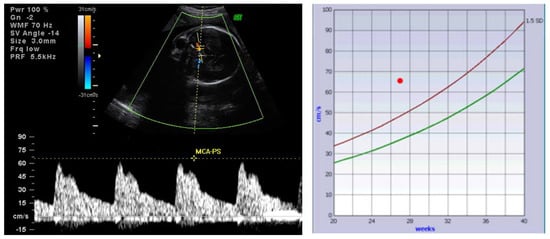

4.1. Alloimmune Hemolytic Disease of the Fetus and Newborn (HDFN)—Anti-Red Cell Antibodies

- Panaitescu, A.; Nicolaides, K. Fetal Goitre in Maternal Graves’ Disease. Acta Endocrinol. (Buchar.) 2018, 14, 85–89. [Google Scholar] [CrossRef]